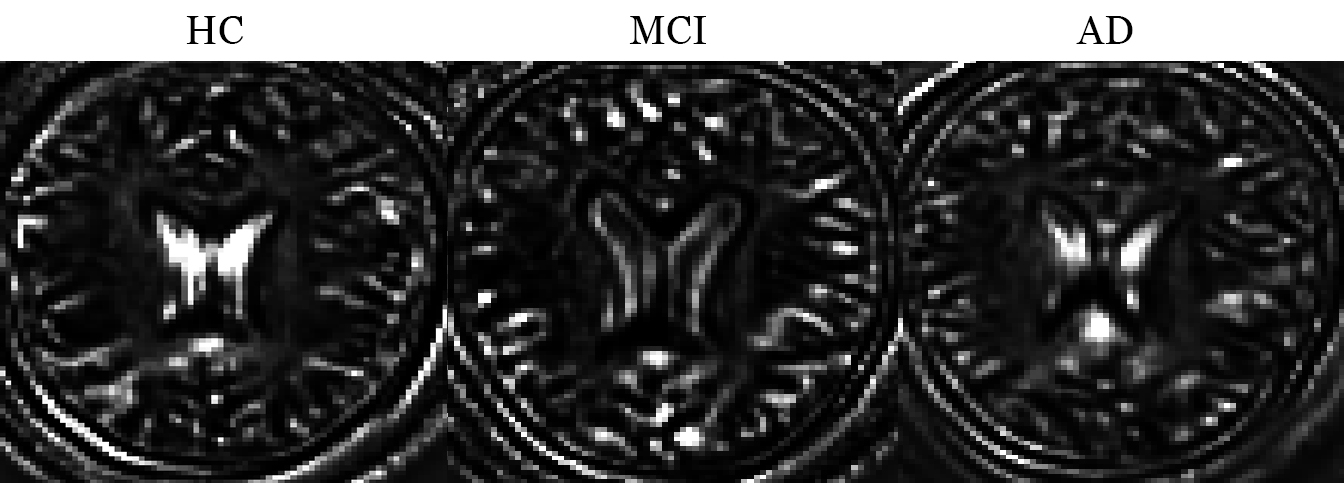

The interpretation of our results is made difficult by the nature of the deep neural network architectures. Figure 3 shows the convolutions of MRI scans from each of the 3 classes with the fourth basis of the 3D sparse autoencoder.

Refer to caption

Figure 3: Examples of convolutions with the fourth basis of the 3D sparse autoencoder (32nd slice). An example from each class is randomly chosen.